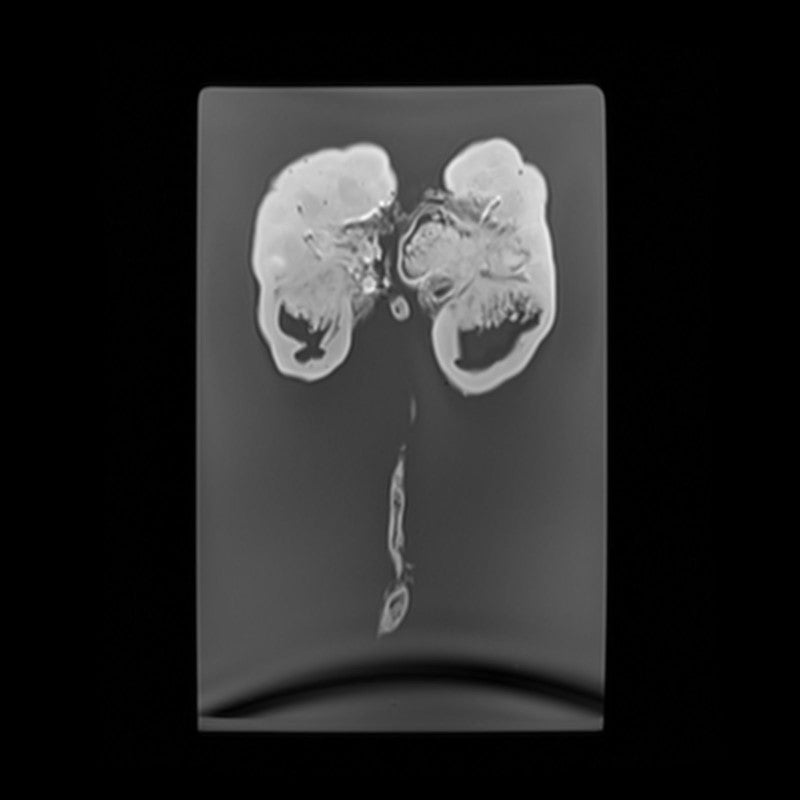

Kidney and Adrenal - Normal